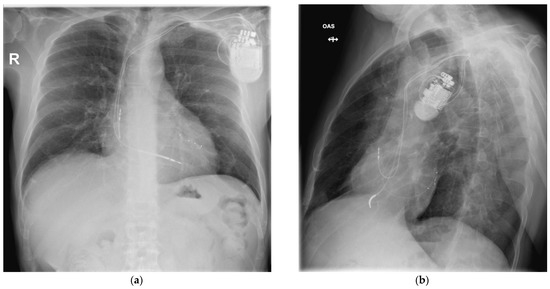

Post-procedural echocardiography revealed no pericardial effusion, no additional tricuspid valve dysfunction, and no lead fragments. The control chest X-ray after the procedure revealed the leads were in normal positions, as shown in Figure 7.

Figure 7. CRT-D system with leads in normal positions: (a) posteroanterior view and (b) left anterior oblique view.